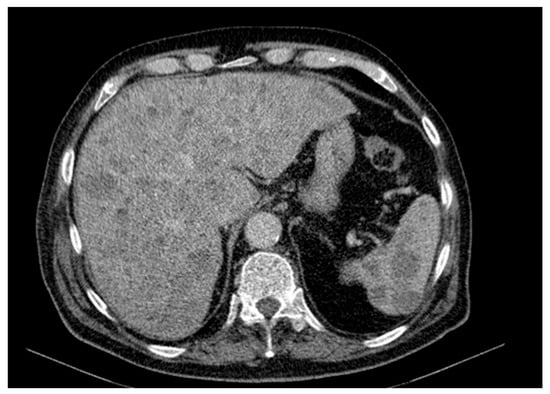

Background and Clinical Significance: Merkel cell carcinoma (MCC) is a rare, aggressive neuroendocrine cutaneous malignancy with increasing incidence among elderly, immunocompromised patients or individuals exposed to ultraviolet radiation. Case Presentation: We present the case of an 84-year-old Caucasian male with no history of [...] Read more.

Background and Clinical Significance: Merkel cell carcinoma (MCC) is a rare, aggressive neuroendocrine cutaneous malignancy with increasing incidence among elderly, immunocompromised patients or individuals exposed to ultraviolet radiation. Case Presentation: We present the case of an 84-year-old Caucasian male with no history of immunosuppression, who was admitted for asthenia, dysphagia, weight loss, and generalized weakness. Clinical and imaging investigations revealed a violaceous tumor on the right arm and disseminated metastases affecting the liver, spleen, bones and lymph nodes. A liver biopsy confirmed a small round blue cell neoplasm suggestive for MCC, although immunohistochemistry could not be performed due to the patient’s fulminant deterioration and death within 12 days of admission. Conclusions: This case is notable for its exceptionally rapid progression, particularly splenic involvement, and absence of known immunosuppressive factors. It highlights the existence of highly proliferative MCC subtypes with potential for bypassing classical metastatic pathways. Early clinical suspicion and prompt histological evaluation are essential for diagnosis, although the prognosis remains poor in advanced stages. Due to fulminant deterioration, immunohistochemistry could not be performed; therefore, the diagnosis is highly suggestive based on clinical, imaging, and morphological correlation. Full article